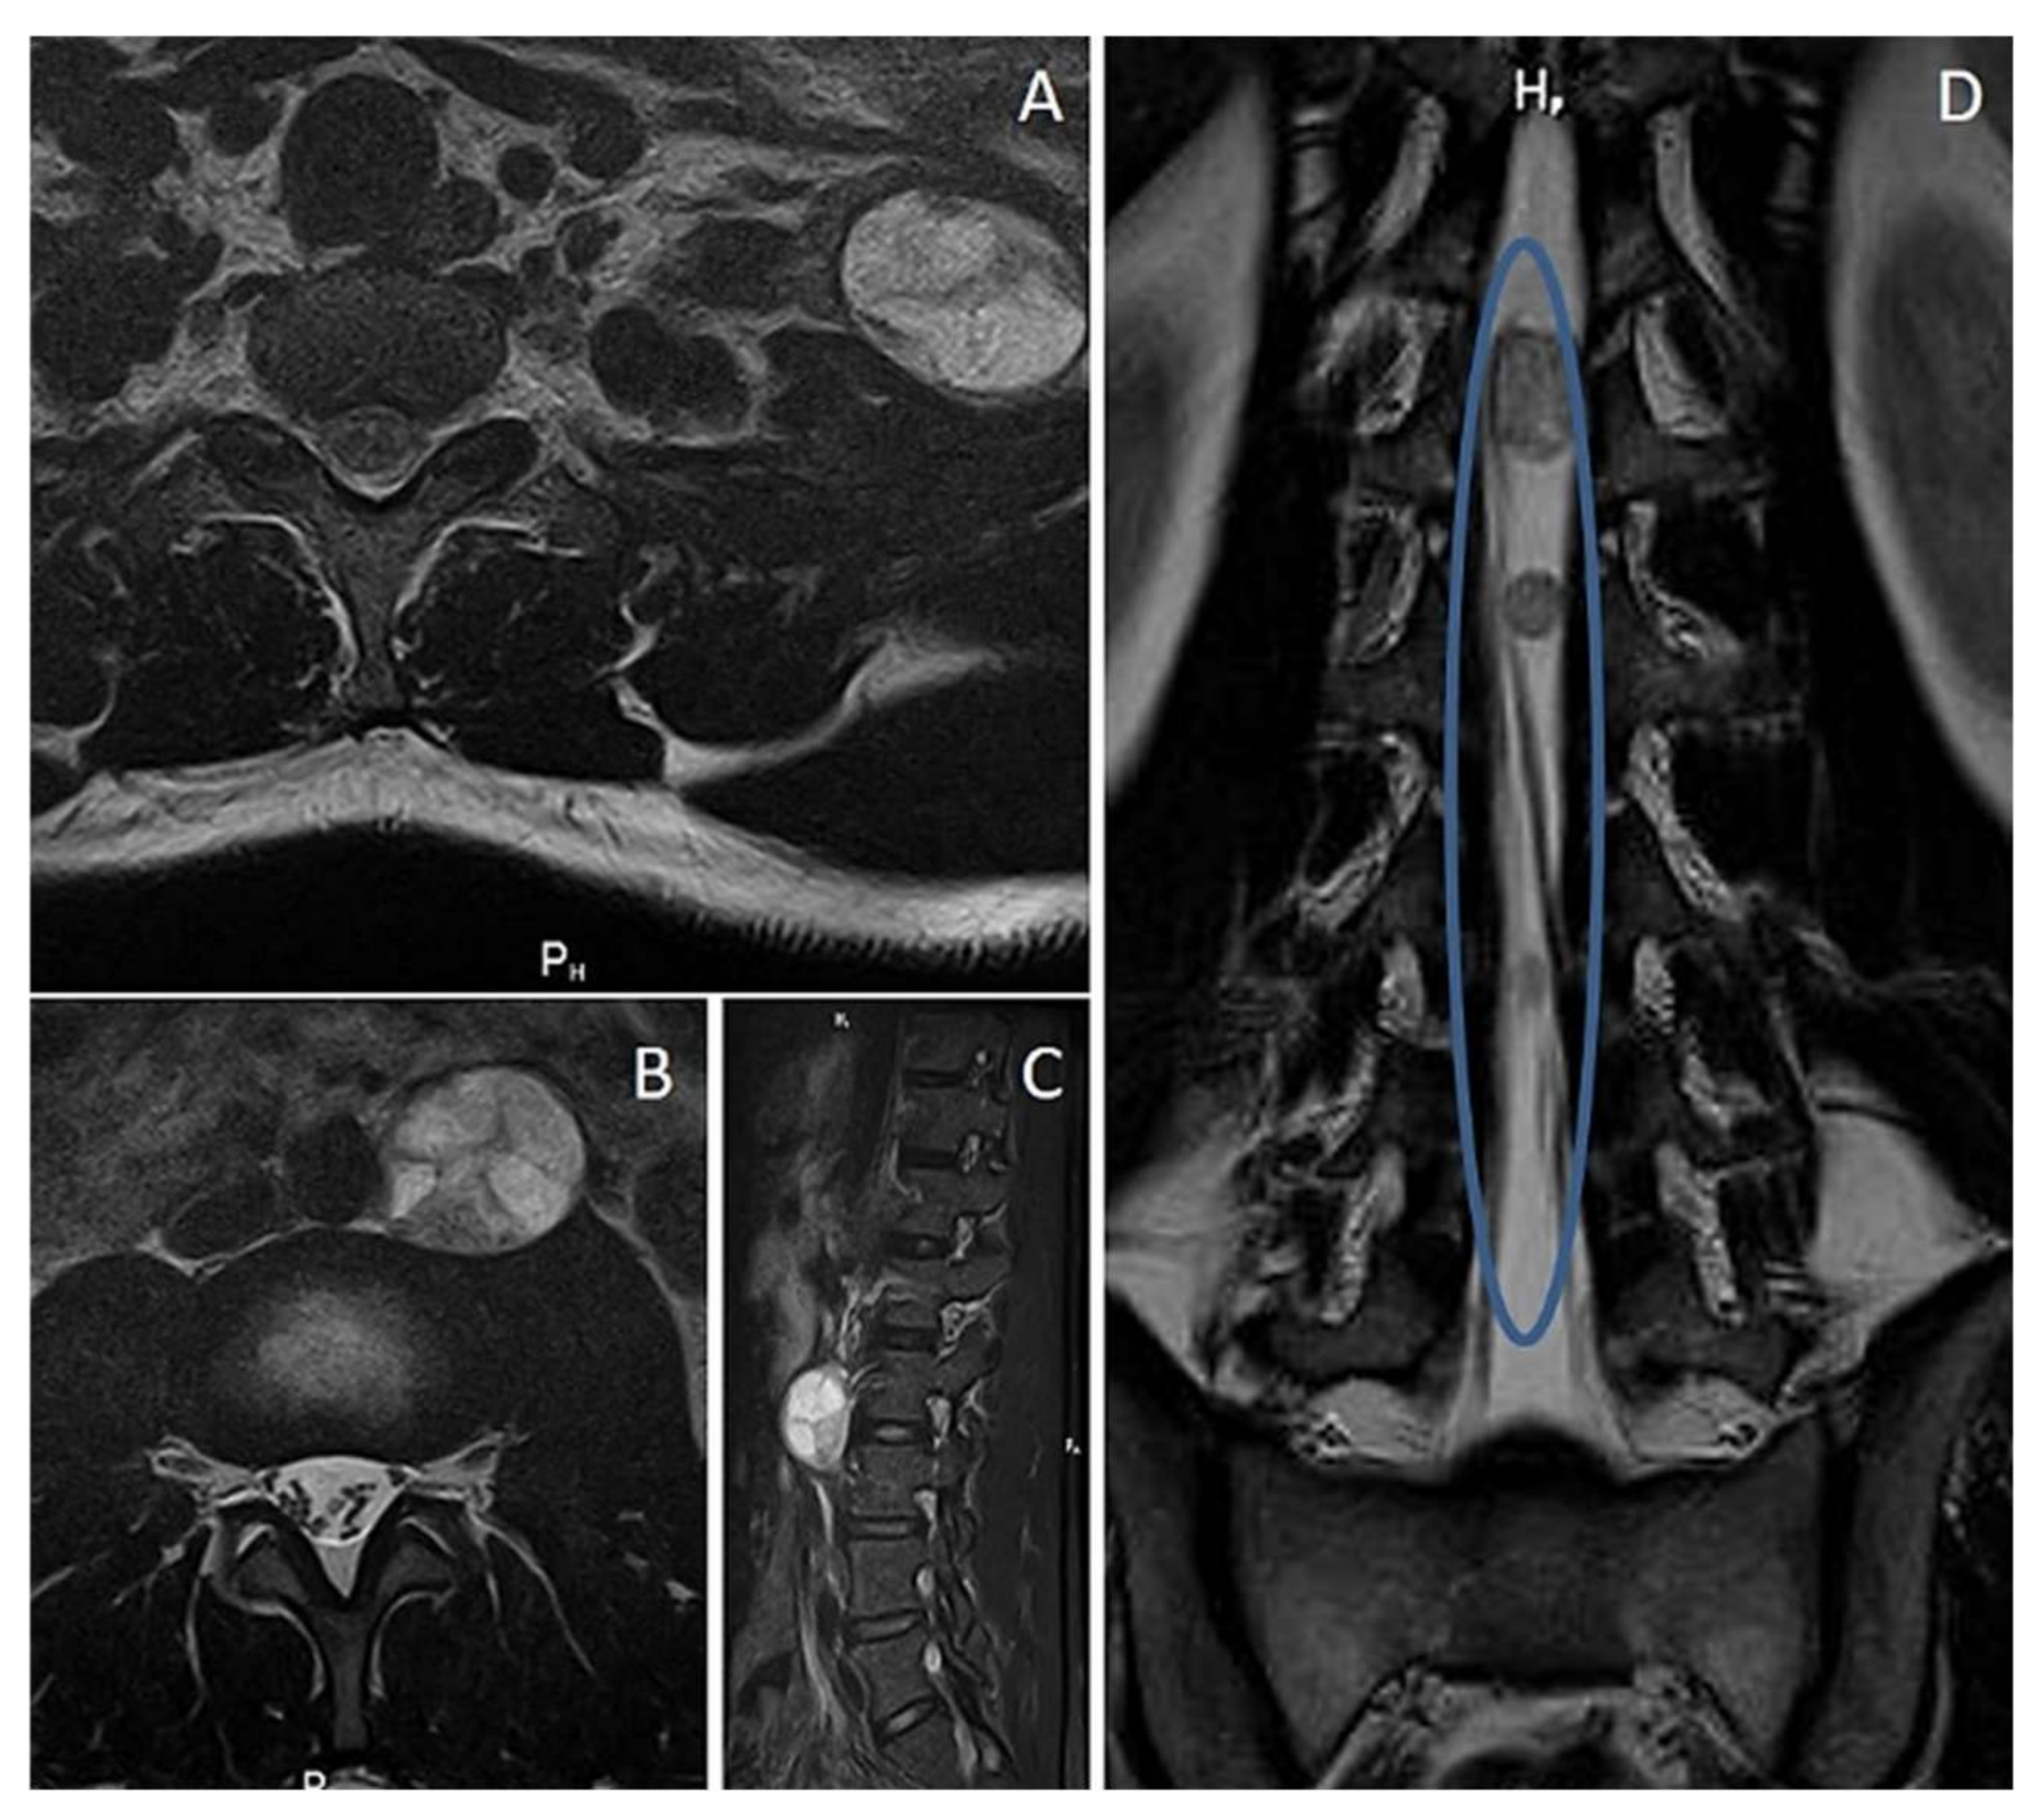

3.3. Plexiform Neurofibroma